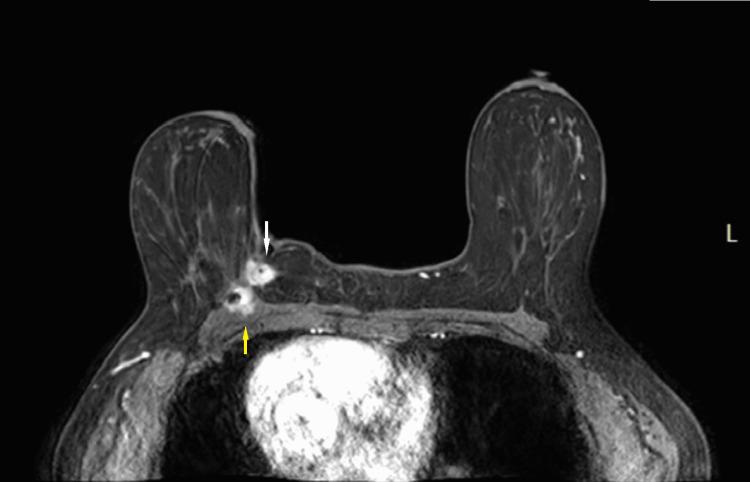

We describe a case of pathology-proven invasive lobular breast cancer (ILC) arising in a scar over 15 years after lumpectomy for previous invasive ductal carcinoma (IDC). The tumor was detected on screening mammography as a new focal asymmetry at the scar site and confirmed at diagnostic mammography. Ultrasound demonstrated an irregular, shadowing, hypoechoic mass at the scar site. Ultrasound-guided biopsy revealed poorly differentiated invasive lobular carcinoma. MRI and CT showed an irregular mass with pectoralis muscle invasion. Multimodality imaging findings are described. This is the first case to our knowledge reporting multimodality imaging findings of a breast cancer developing at the site of a surgical scar that is histologically different from the originally resected cancer.

我们描述了一例经病理证实的浸润性小叶乳腺癌(ILC)病例,该病例发生于先前因浸润性导管癌(IDC)行肿块切除术后15年以上的瘢痕处。肿瘤在筛查乳腺X线摄影中被检测为瘢痕部位新出现的局灶性不对称,并在诊断性乳腺X线摄影中得到证实。超声显示瘢痕部位有一个不规则、有阴影、低回声肿块。超声引导下活检显示为低分化浸润性小叶癌。MRI和CT显示有一个不规则肿块,侵犯胸大肌。描述了多模态成像结果。据我们所知,这是首例报告手术瘢痕部位发生的组织学上与最初切除的癌症不同的乳腺癌的多模态成像结果的病例。